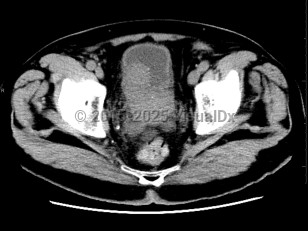

Most prostate cancers are identified at the local stage through annual screenings, and the majority of patients are asymptomatic at that stage. At later stages, physical findings may include perineal pain and urinary changes (eg, frequency, retention, nocturia). Urinary changes in men are more frequently the result of benign prostate conditions, which are sometimes found as comorbidities. Physical examination may reveal areas of induration, asymmetry, and/or prostate nodule. Diagnosis is confirmed via prostate biopsy.

If cancer has spread, physical findings may include bone pain or pathologic fracture. See metastatic prostate carcinoma.